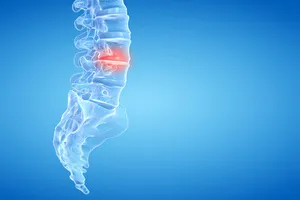

척추관협착증은 척추뼈 안쪽 통로인 척추관이 좁아져 신경을 압박하여 허리 통증, 다리 저림, 감각 이상 등의 증상을 유발하는 질환입니다. 이러한 증상이 심하거나 보존적인 치료(약물 치료, 물리치료 등)에도 불구하고 호전되지 않을 경우 수술적 치료를 고려하게 됩니다.

수술의 목적은 좁아진 척추관을 넓혀 신경을 압박하는 요인을 제거하고, 이로 인해 발생하는 통증과 신경 증상을 완화시키는 것입니다.